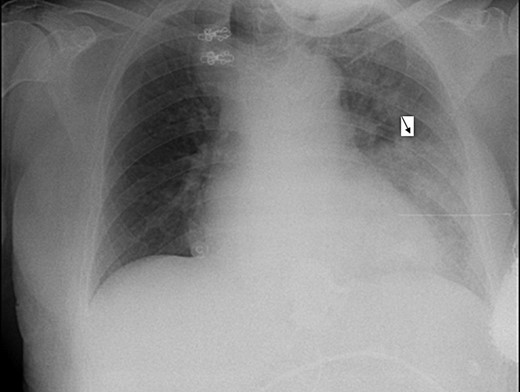

Electrocardiogram was remarkable for Q waves in leads I, aVL and V6. Chest X-ray (CXR) demonstrated a marked esophageal distention with an air fluid level (Figs 1 and 2).

Anterio-posterior CXR views demonstrate the shadow of a dilated esophagus and air fluid level (black arrow).

During her hospitalization, the patient developed fever and desaturation, with a new infiltrate on CXR (Fig. 3). She was diagnosed with pneumonia and was treated with antibiotics. Later on, after significant improvement, though still suffering from a barking cough (attributed to reflux), the patient left her bed and in an attack of severe coughing, lost consciousness, fell and became cyanotic. Repeated attempts to improve oxygenation failed until a naso-gastric tube was inserted with drainage of ∼1 l of non-bilious content, resulting in rapid improvement in the patient's condition. A repeat CXR revealed the naso-gastric tube in her esophagus. Repeated attempts to insert the NGT into her stomach failed, even with the aid of contrast media. The silastic band was then deflated, allowing for less restriction, and an endoscopy showed esophagitis but no obstruction.